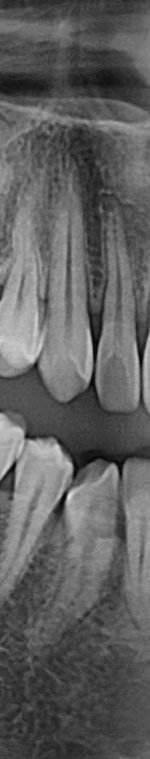

턱 뼈와 치아 사이에 공간이 충분하지 않기 때문에 누워서 올라오거나 매복되어 자라는 경우가 많았어요. 반포치과를 찾는 분들의 사랑니의 경우 매복된 경우도 많고 이가 완전히 잇몸 밖으로 나오지 않아서 일반 치과에서는 발치가 어려웠어요. 사랑니발치가 왜 필요한지 가끔 의문을 가지는 분이 계셨어요. 사랑니발치를 왜 해야 하는지 알려드리겠어요. 사랑니는 다른 치아처럼 바르게 나는 경우도 드물게 있긴 하지만 대부분 어금니 쪽으로 기울어져서 올라오거나, 완전히 수평으로 누워서 자라는 경우도 있었어요. 누워서 자라는 치아는 옆의 치아를 밀어 치열이 비뚤어지고 부정교합을 유발했어요.

사랑니가 90도로 누워서 난 경우는 수평 매복, 뼈나 잇몸에 사랑니가 완전히 덮여서 아예 보이지 않는 경우는 완전 매복, 일부분만 잇몸이나 뼈에 덮여있는 경우 부분매복이라고 했어요. 대부분의 환자분이 이런 매복 중에 한 가지에 해당하기 때문에 시술이 매우 어려웠어요. 특히 사랑니 주변으로는 구강과 관련된 중요한 신경 조직이 인접하여 있기 때문에 고난이도 시술이라고 할 수 있었어요.

만약 사랑니 발치 시술이 잘못되면 사랑니와 인접한 신경 조직에 손상이 오거나 구강 마비와 같은 부작용이 발생할 수 있었어요. 그렇기 때문에 사랑니 발치를 하기 위해 치과를 선택할 때는 신중하게 선택해야 했었어요. 반포치과를 선택하기 전에 발치전문 의료진이 있는지, 경험이 풍부한지 반드시 확인해보시고 결정하셔야 했었어요.

사랑니발치를 하기 위해서는 먼저 파노라마 x선 사진을 통해 발치 시 신경에 영향을 줄 수 있는지 확인하는 과정을 진행했어요. 이 과정을 통해서 충분히 의사와 상담을 한 후 처방전을 발급했어요. 이 때 처방전에는 항생제를 포함하여 발치 후 통증을 대비한 진통제를 처방했어요. 환자에게 충분히 설명한 후에 국소마취를 진행하고 마취가 된 다음에 절개를 최대한 덜 하는 방향으로 수술하여 사랑니를 발치했어요.